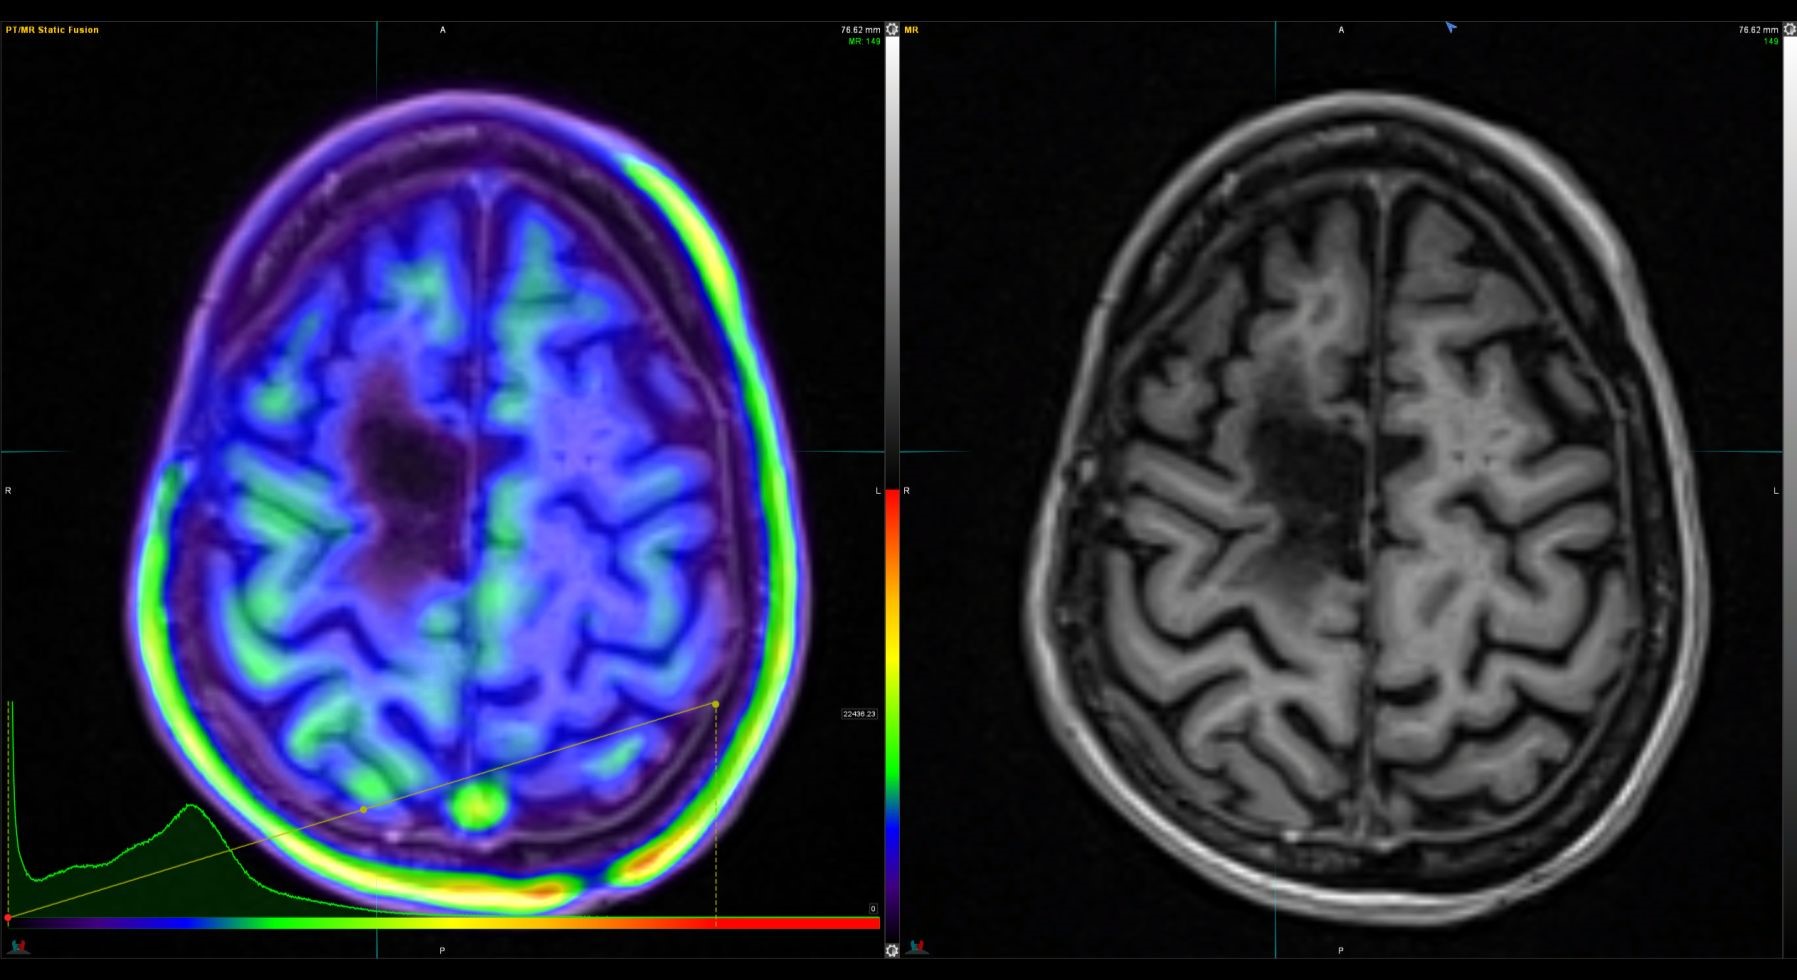

Η Τομογραφία Εκπομπής Ποζιτρονίων (PET) αποτελεί μια εξειδικευμένη μέθοδο της Πυρηνικής Ιατρικής που χρησιμοποιεί μοριακή απεικόνιση για να εντοπίσει και να παρακολουθήσει φυσιολογικές και παθολογικές λειτουργίες του οργανισμού. Συνδυάζοντας τη λειτουργική απεικόνιση της PET με την ανατομική πληροφορία της αξονικής τομογραφίας (CT), η υβριδική εξέταση PET/CT παρέχει εικόνες υψηλής ευκρίνειας και τη δυνατότητα ποσοτικής αξιολόγησης των βιολογικών μηχανισμών σε κυτταρικό επίπεδο.

Η PET/CT αποτελεί εξαιρετικά προηγμένη τεχνική της σύγχρονης ιατρικής απεικόνισης και χρησιμοποιείται τόσο για τη διάγνωση όσο και για την παρακολούθηση της ανταπόκρισης στη θεραπεία.

Οι κυριότερες εφαρμογές της αφορούν την ογκολογία, τη νευρολογία και, σε μικρότερο βαθμό, την καρδιολογία, ενώ συνεχώς αναπτύσσονται νέες χρήσεις σε άλλες ιατρικές ειδικότητες.

Στο Κέντρο PET/CT πραγματοποιούνται εξειδικευμένες εξετάσεις που καλύπτουν ένα ευρύ φάσμα κλινικών εφαρμογών στη σύγχρονη Πυρηνική Ιατρική. Ανάλογα με το είδος του προβλήματος και τη φύση της νόσου, χρησιμοποιούνται διαφορετικά ραδιοφάρμακα για τη μελέτη συγκεκριμένων βιολογικών μηχανισμών.